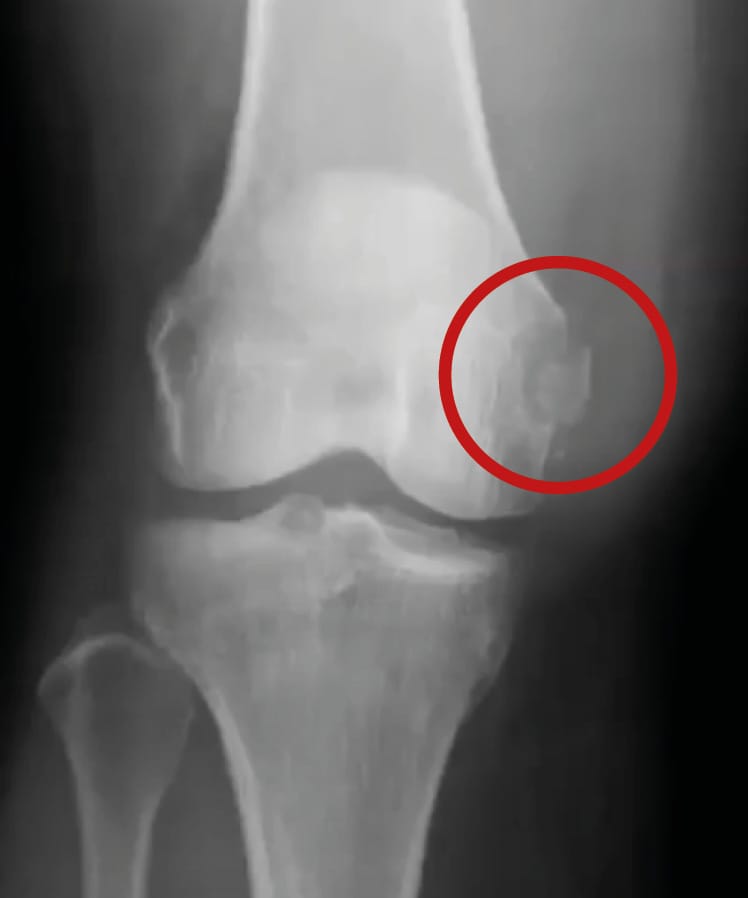

• Radiography: Weight-bearing plain film radiographs (AP, lateral and femoropatellar) are the first investigations to perform. In the acute phase, these are able to detect associated bone injuries (fractures, avulsions) (figure 6) and any soft tissue swelling.

In the chronic phase, stress radiographs are also used to measure opening of the joint space under valgus forces (figure 7). Bilateral radiographs must be taken for comparison. An increase exceeding 3 mm in 30° of flexion demonstrates a complete tear of the sMCL, an increase of around 10 mm indicates an sMCL and dMCL injury and exceeding 10 mm is a combined MCL and POL injury, often in conjunction with an injury to one or both cruciate ligaments [8] Laprade RF, Bernhardson AS, Griffith CJ, Macalena JA, Wijdicks CA. Correlation of valgus stress radiographs with medial knee ligament injuries: an in vitro biomechanical study. Am J Sports Med. févr 2010;38(2):330-8. .

Down the line from a trauma, Pellegrini-Stieda disease may also be evaluated, as this is ossification of the MCL at its femoral insertion seen on radiography (Figure 4) in conjunction with chronic pain (Figure 8). The main differential diagnosis is chondrocalcinosis deposits in the medial recess.